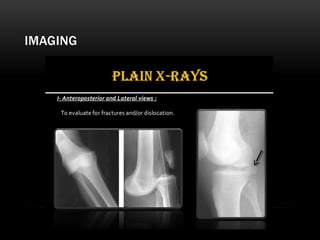

IMAGING

A- PCL INTACT KNEE DISLOCATION

B- BICRUCIATE – Parallel arrangement of patella with femur